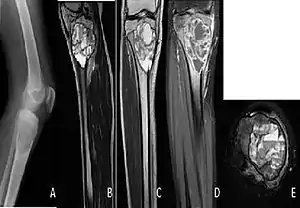

| A. X-ray: osteolytic lesion in tibia near knee. B/C/D/E. MRI with E showing fluid levels. | |

The cause is unknown.[1] Diagnosis involves medical imaging.[1] CT scan and X-ray show lytic expansion lesions with clear borders.[1] MRI reveals fluid levels.[1]

X-ray and CT scan show lytic expansion lesions with clear borders.[1] Expansion of cortex gives the lesion a balloon-like appearance. Larger lesions may appear septated.[11] MRI reveals fluid levels.[1] Bone scan shows outer radiotracer uptake, with a central dark area.[1][11]